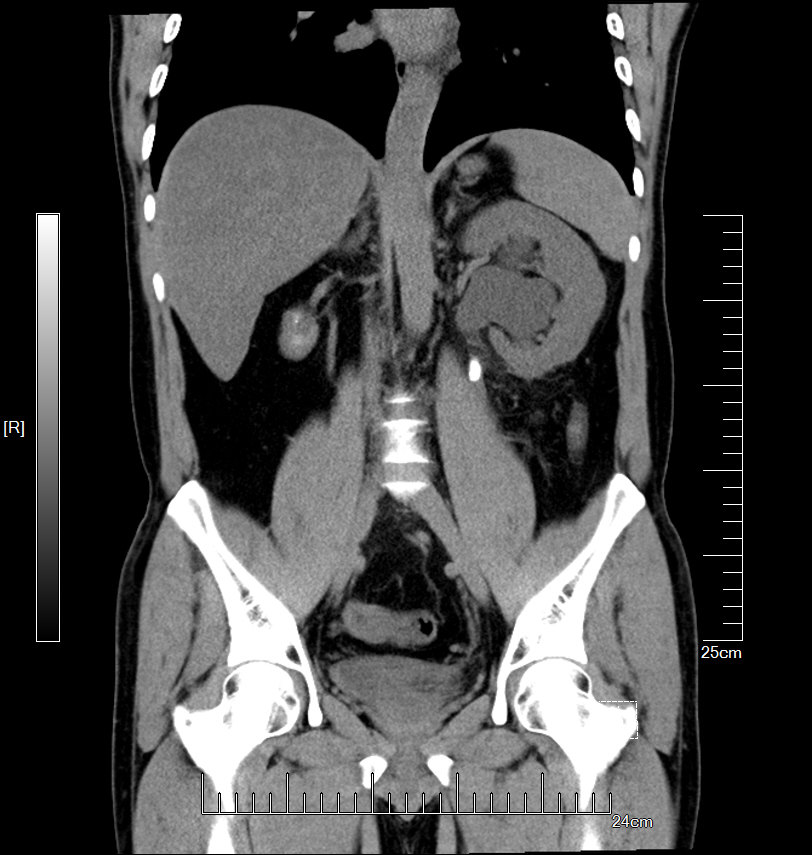

增强CT检查提示:左侧肾脏重度积水 皮质菲薄,几乎已无功能

左侧输尿管结石约1.5cm

GFR:左侧仅4.89ml/min,与增强CT检查相符

2016年04月手术患者,男性,37岁,盐城人,十七年前曾因左输尿管结石引起肾绞痛在当地予以多次震波碎石,疼痛缓解后未于重视,其间未予复查,一直于当地务农,自称今年来苏打工,招工体检时发现左肾重度积水一周来院求诊;CT:左侧肾脏重度积水,皮质菲薄,左侧输尿管结石约1.5cm,GFR:左侧4.89ml/min,右侧56.9ml/min。因右侧健肾代偿,肾功能正常:Cr 98umol/L;术前诊断:左输尿管结石 左肾重度积水 左肾无功能,鉴于左输尿管结石梗阻时间太长,左肾已几乎无功能,呈现皮囊肾样改变,最终只能行腹腔镜下左侧肾输尿管切除术,一并取出皮囊肾和输尿管及结石。